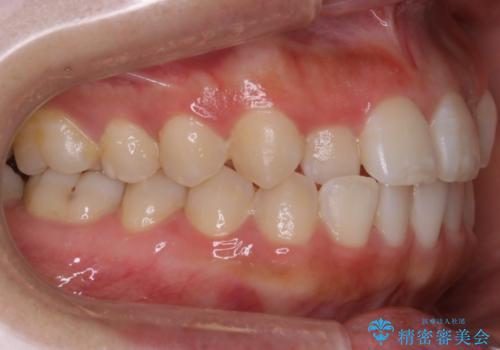

【非抜歯】部分矯正でも治る 前歯の反対咬合

- 前歯にガタつきを主訴にご来院されました。

奥歯の嚙み合わせに問題がほとんどみられなかったため、インビザライン ライトパッケージでの部分矯正を行うこととなりました。

今回のケースでは奥歯の噛み合わせに問題がほぼみられなかったため、前歯の位置のみに焦点を当て部分矯正を行いました。